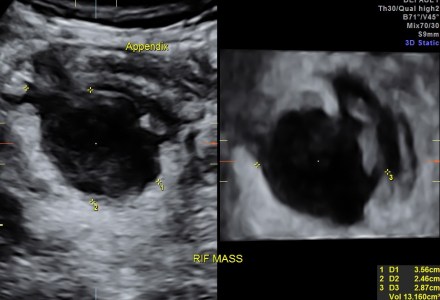

Appendicular mass